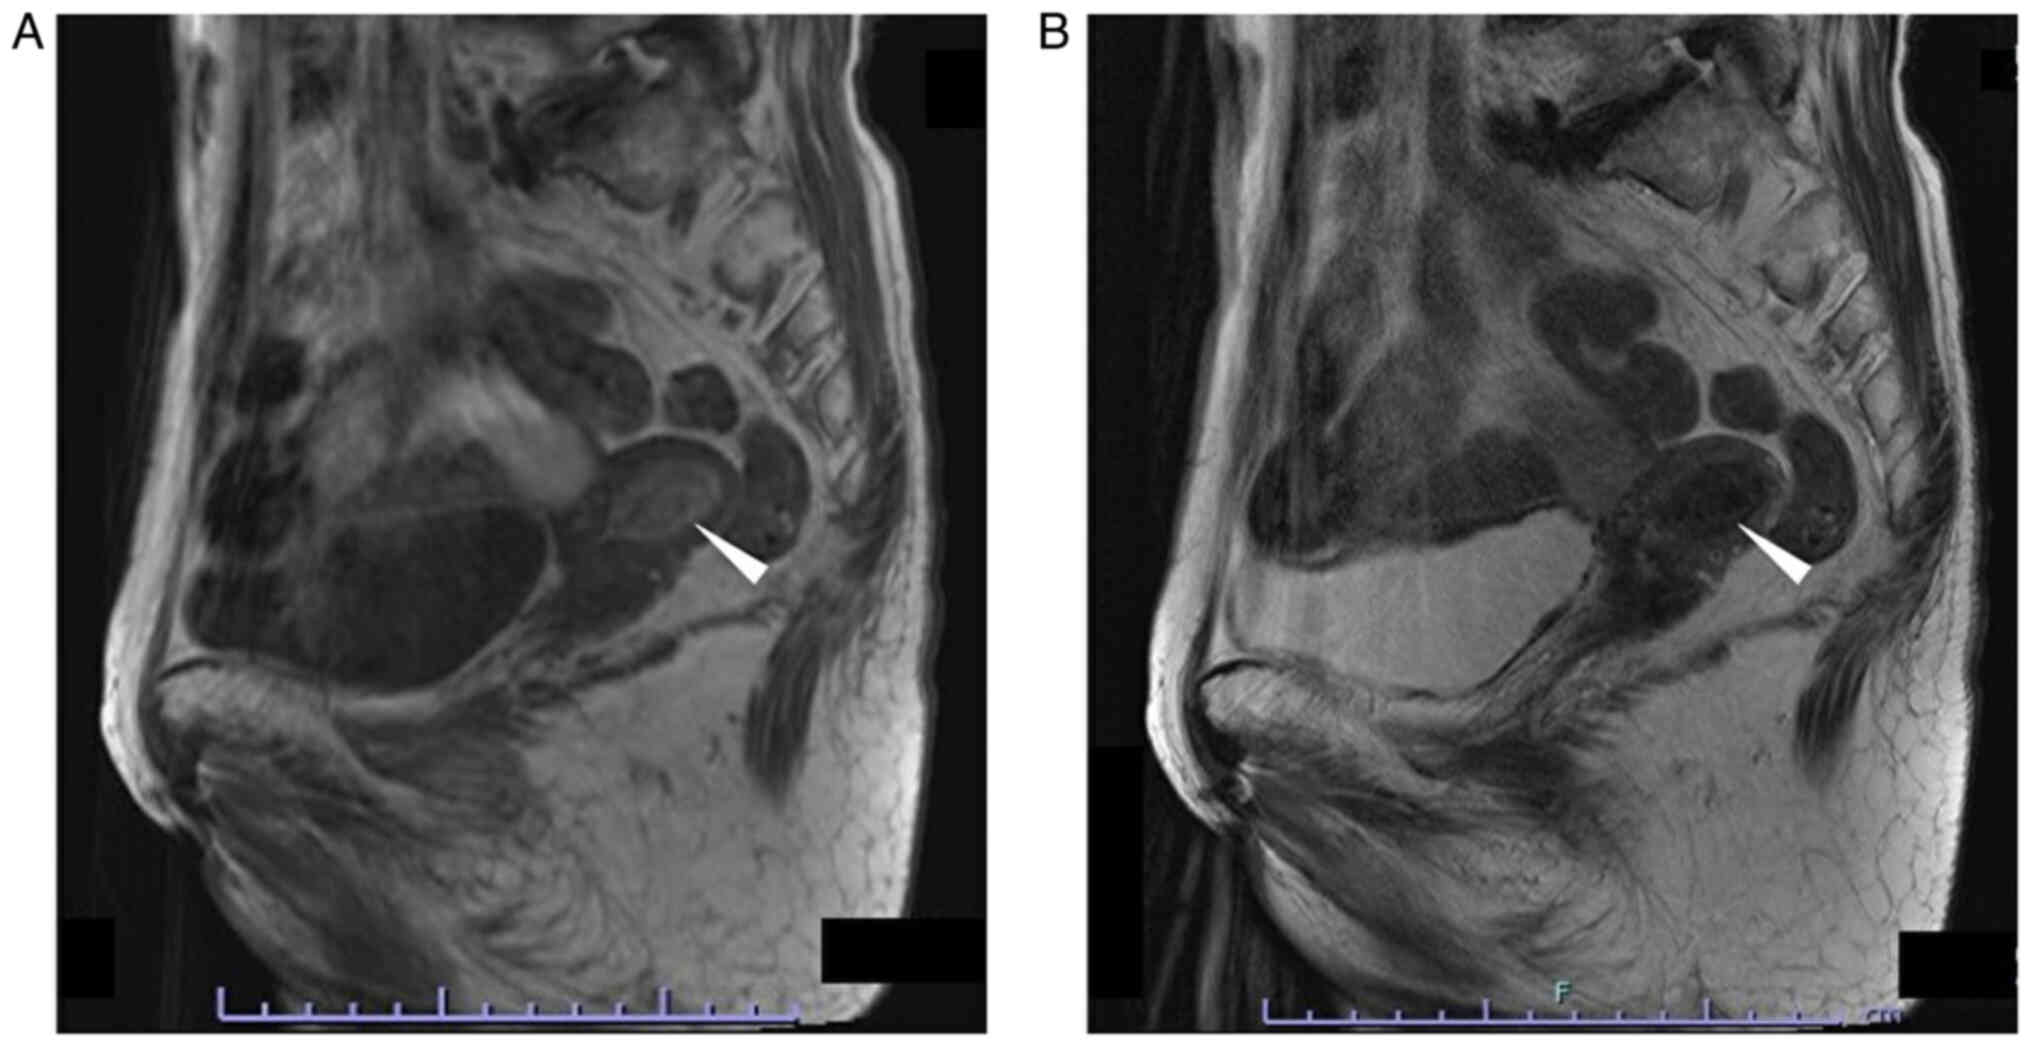

The patient was an 80-year-old gravida 4 para 3 female who had experienced menopause around the age of 50 years. The patient had undergone an appendectomy at age 13 and surgery for rhino polyps at age 74. In addition, the patient had received surgery and radiotherapy for vulvar Paget's disease at the Department of Dermatology of Osaka Metropolitan University Hospital (Osaka, Japan) at age 79. Regarding the family history of the patient, the brother of the patient had gastric cancer. After the surgery (tumorectomy) and radiotherapy (radiation dose, 60 Gy; fractionation, 30) for vulvar Paget's disease, the patient was followed up at the outpatient department of the Department of Dermatology, where a uterine tumor was accidentally identified by CT (Aquilion ONE; Canon, Inc.) 1 year after surgery (Fig. 1A). Therefore, the patient was referred to the Gynecological Department of Osaka Metropolitan University Hospital (Osaka, Japan). The patient experienced no subjective symptoms, such as abnormal genital bleeding or abdominal pain. A vaginal examination revealed uterine bleeding that was unremarkable and not abnormal. Transvaginal ultrasonography (Aplio a450; Canon, Inc.) showed a high-intensity mass in the uterine cavity (Fig. 1B). Tumor markers revealed that the serum levels of carcinoembryonic antigen (CEA) measured using CEA Abbott Alinity G06290R04, carbohydrate antigen (CA)19-9 measured using CA19-9 XR Abbott Alinity G06327R03, CA125 measured using the CA125 II Abbott Alinity G06330R04 (all from Abbott Molecular Inc.) and sialyl-Tn measured using the STN Otsuka RIA kit (Otsuka Assay Laboratories) (all measurements taken according to the manufacturer's instructions) were within normal ranges as follows: CEA <1.7 ng/ml (normal range, ≤5.0 ng/ml); CA19-9, 3 U/ml (normal range, ≤37.0); CA125, 16 U/ml (normal range, <35.0 U/ml), sialyl-Tn, 16.0 U/ml (normal range, ≤45.0), with blood tests indicating no other abnormal findings. MRI revealed a 25×15-mm mass, which was of low intensity in the tumor (T)2-weighed images, but of high intensity in the T1-weighted images (version 3.0; Philips Ingenia). In addition, the mass of the patient had high intensity in the diffusion-weighted images, but low intensity in the apparent diffusion coefficient map, which suggested the presence of a malignant tumor in the uterine cavity. There were no abnormal lesions in the uterine cervix, suggesting that there was no cervical invasion or malignancies of cervical origin (Fig. 2).

Figure 2.

MRI. (A) T1-weighted image. A 26.6×16.6-mm, high-intensity lesion was detected in the uterine cavity (white arrowhead). Repetition time, 500 msec; echo time, 12 msec; flip angle; 150°. (B) T2-weighted image. A 26.6×16.6-mm sized low-intensity lesion was detected in the uterine cavity (white arrowhead). Repetition time, 4,000 msec; echo time, 97 msec; flip angle, 140°. T, tumor.